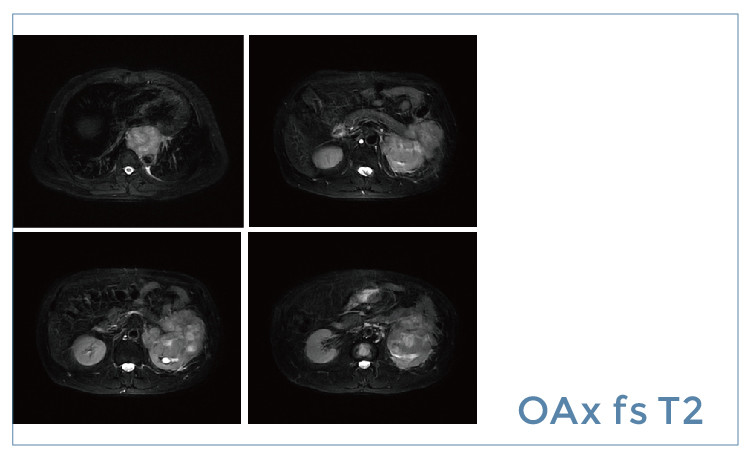

【朗润影像档案】20190517磁共振影像病例结果讨论

朗润影像档案】磁共振影像病例分享(编号20190517)